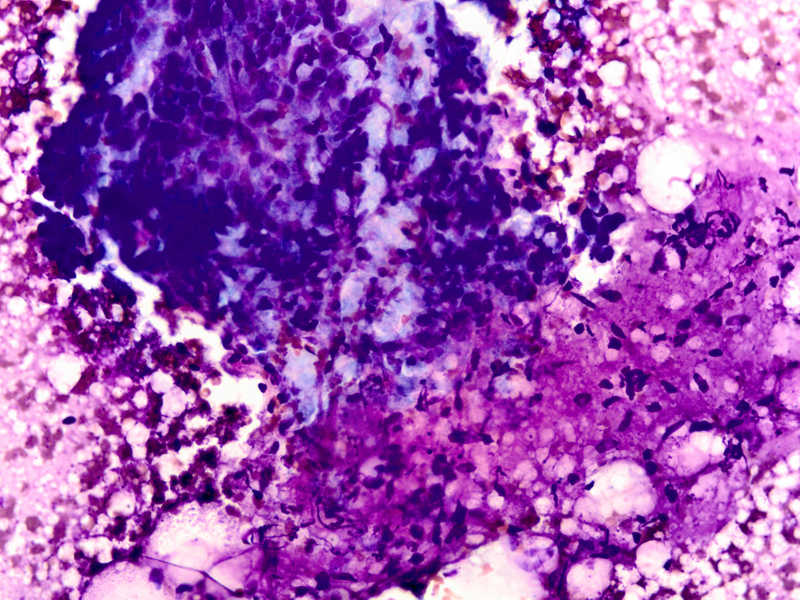

A 64 year old postmenopausal female presented with a 1.5 cm mass in the upper, outer quadrant of her left breast. On mammography this was an isodense lobulated mass. Ultrasonography revealed a solid, hypoechoic complex cystic mass. The patient underwent a fine needle aspiration.

• Fig 1: FNA cytology, Diff-quik stain, X40

Cytologic findings

• Moderately cellular smear

• Branching clusters of ductal epithelial cells, dissociated single cells, or rarely acinar or papillary arrangements

• Polygonal to round ductal epithelial cells with uniform nuclei, abundant cytoplasm and inconspicuous nucleoli

• Focal marked atypia may be seen in benign adenomyoepitheliomas (1).

• Abundant myoepithelial cells as round to spindled shaped cells, as bare oval nuclei in the background or overlying epithelial cell clusters, or as cells with clear cytoplasm

• Focal aggregates of spindled cells

• Fragments of myxoid or fibrous stroma

• Intranuclear inclusions (1) and intracytoplasmic vacuoles (2) have been described

• Thin proteinaceous debris, histiocytes and apocrine cells may be seen

Discussion: Adenomyoepithelioma was first reported by Hamperl in 1970 as an uncommon biphasic tumor composed of epithelial and myoepithelial cells (3). Adenomyoepitheliomas usually present as a single circumscribed mammary nodule. The fine needle aspiration findings in adenomyoepitheliomas have been described in only a few reports (1, 2, 4-11). It is important to recognize this entity as the radiologic and cytologic features can mimic malignancy. On cytology single enlarged atypical epithelial cells, presumed to be of myoepithelial origin due to staining with S-100 protein have been noted and led to the erroneous diagnosis of carcinoma (6). Only rarely can this diagnosis be made definitively on fine-needle aspiration biopsy (7). Histologic patterns include the tubular, lobulated and spindle cell variants (12). Biphasic pattern consists of tubules lined by cuboidal or columnar shaped epithelial cells surrounded by myoepithelial cell layer, Malignant adenomyoepitheliomas are usually characterized by cellular pleomorphism, necrosis, high mitotic activity and invasion of the surrounding tissue. Immunohistochemistry illustrates the biphasic nature of adenomyoepitheliomas with staining for low molecular weight cytokeratin and epithelial membrane antigen in the epithelial component and staining for smooth muscle actin, S-100 protein, calponin, p63 and maspin in the myoepithelial cell component (8)